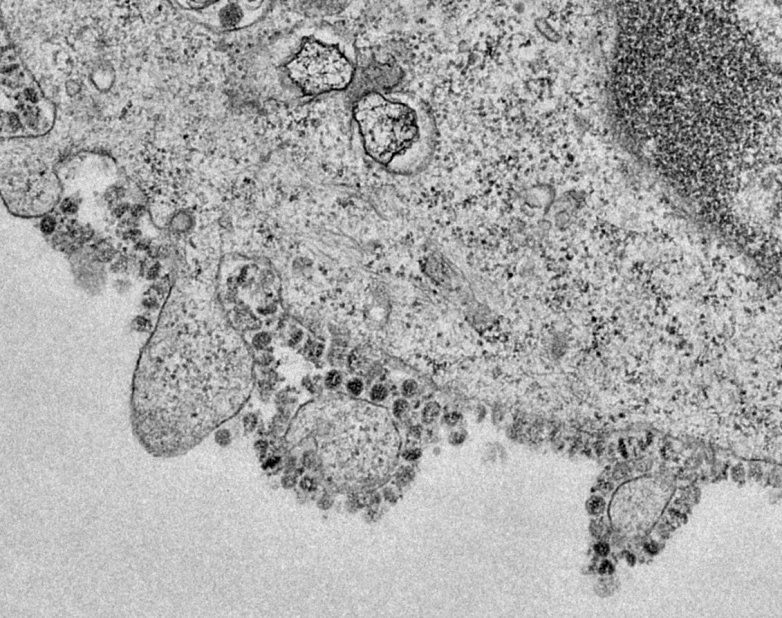

Canine Coronavirus (CCoV) is a highly contagious intestinal infection. Originally identified in 1971, the virus usually produces mild gastroenteritis in infected dogs. It comes from the Coronaviridae family. The virus, when viewed with a microscope, looks like a crown with ornaments fixed on a metal ring. There are several strains of coronavirus, each affecting different animals including humans.